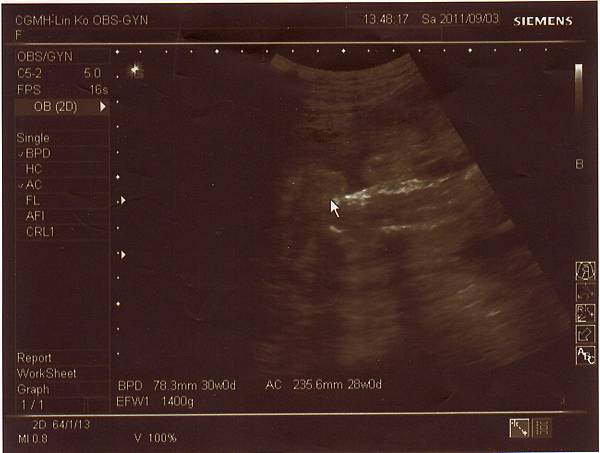

2011.09.03 兔寶妹已經三十週囉!

不僅胎位已經正了(醫生還說姿勢一百),體重也很正常來到1400公克,

連醫生都說看起來肚子不大但孩子卻長得很好呢!